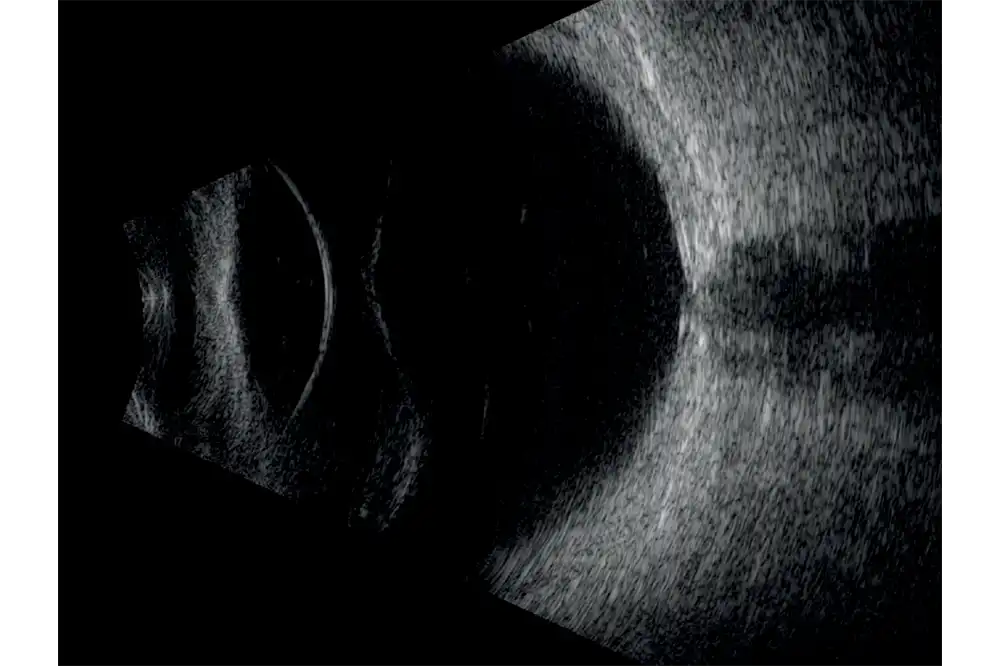

Het volledige oog is nu zichtbaar met een uitstekend detailniveau.

De ringtechnologie verdubbelt praktisch de scherptediepte. De 20 MHz-ringvormige sonde heeft een verlengde scherptediepte van 70%, waardoor het mogelijk is om pathologieën van het glasvocht, het netvlies en verder tegelijkertijd te observeren zonder concessies te doen aan de beeldresolutie.

- Verhoogde scherptediepte waardoor het gehele oog zichtbaar is.

- Hoge resolutie die het mogelijk maakt om van het voorste gedeelte van het glasvocht tot aan de wand te zien.